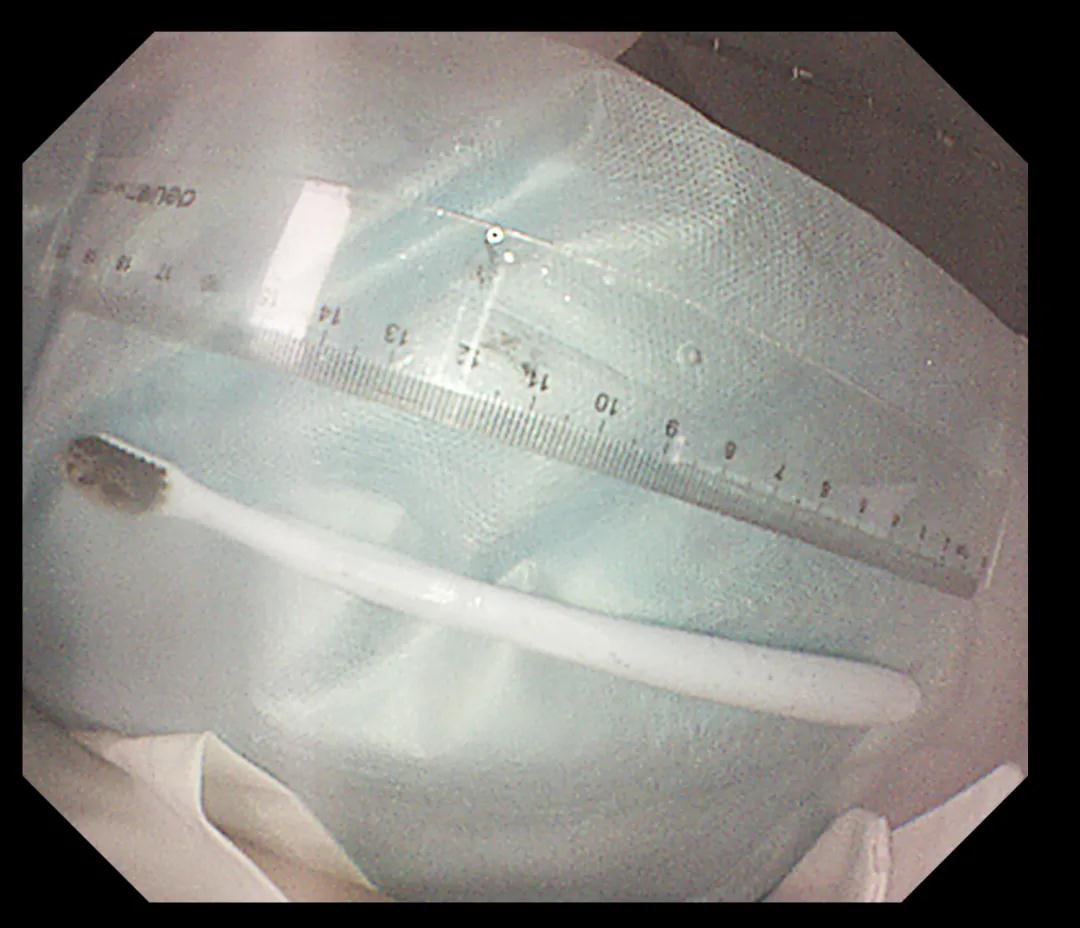

經(jīng)過反復(fù)努力嘗試,圈套器終于緊緊的套住異物,使牙刷長軸盡量與食道長軸平行,適當(dāng)注氣擴(kuò)張食道腔。經(jīng)過不懈努力,順利將其取出,取出牙刷經(jīng)測量長度約20cm,似乎這條細(xì)細(xì)的胃鏡就是一條連接希望的生命線。此時在場所有人懸著的那顆心也終于落下。術(shù)后小楊癥狀逐漸消失,生命指征平穩(wěn),情緒也平靜下來。